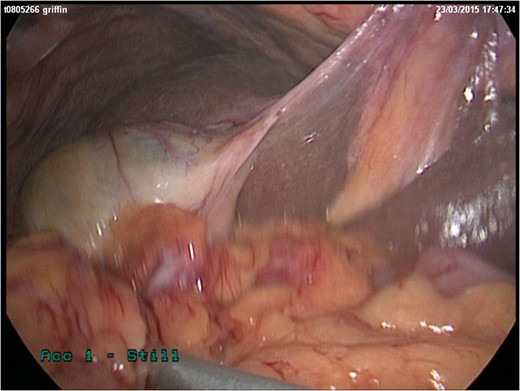

She represented later to our unit with recurrent vomiting. Her investigations revealed a raised lactate and acidosis on arterial blood gas. There was a concern for gastric ischaemia; the decision was taken to proceed to theatre. Given that she was haemodynamically stable with no peritonitis, we chose to operate using a laparoscopic approach. Surgery was performed through four laparoscopy (2Â Ă—Â 11 mm, 2Â Ă—Â 5 mm). A diagnosis of Morgagni hernia was made (Fig. 2). Inside the hernial sac was the transverse colon, the greater curvature of the stomach with a partial gastric volvulus (Fig. 3). The hernia was reduced with the viscera still viable but the sac could not be excised. The defect was repaired with a 6Â Ă—Â 10 cm composite mesh with an absorbable tic fixation on the diaphragm (Fig. 4). No drain was inserted, and the operation time in total was 45 minutes.